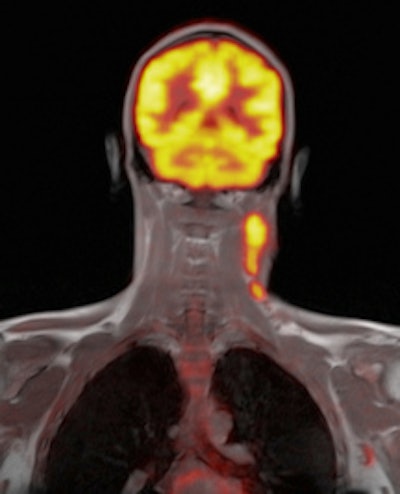

Left: Axial F-18 FDG PET uptake in the same patient is illustrated within the left cervical lymph node in keeping with increased glucose metabolic activity. Right: Coronal Dixon T1-weighted in-phase MR image with superimposed F-18 FDG PET uptake. Left cervical lymphadenopathy is demonstrated in a patient with a known diagnosis of Hodgkin's lymphoma.One of the first commercially available PET/MRI systems is from Siemens Healthcare, Biograph mMR. The scanner has a 60-cm bore and 3-tesla magnet that integrates a ring of solid-state PET detectors that are insensitive to magnetic fields, enabling the system to simultaneously acquire PET and MRI signals.

Brain imaging was one of the first applications for simultaneous PET/MRI systems because the brain is less prone to patient motion. What's more, interest is growing within the neurological community for novel radiopharmaceutical tracers to evaluate neurodegenerative and oncological disease with PET/MRI.

PET/MRI is particularly useful in imaging patients with dementia and Alzheimer's disease, because the combination of high-resolution anatomical, perfusion, and tractography MRI information with F-18 FDG or Pittsburgh Compound B (PiB) PET during a single simultaneous examination creates opportunities for improving the understanding of pathogenesis and mechanism of Alzheimer's disease, and enables early diagnosis and supports drug development.